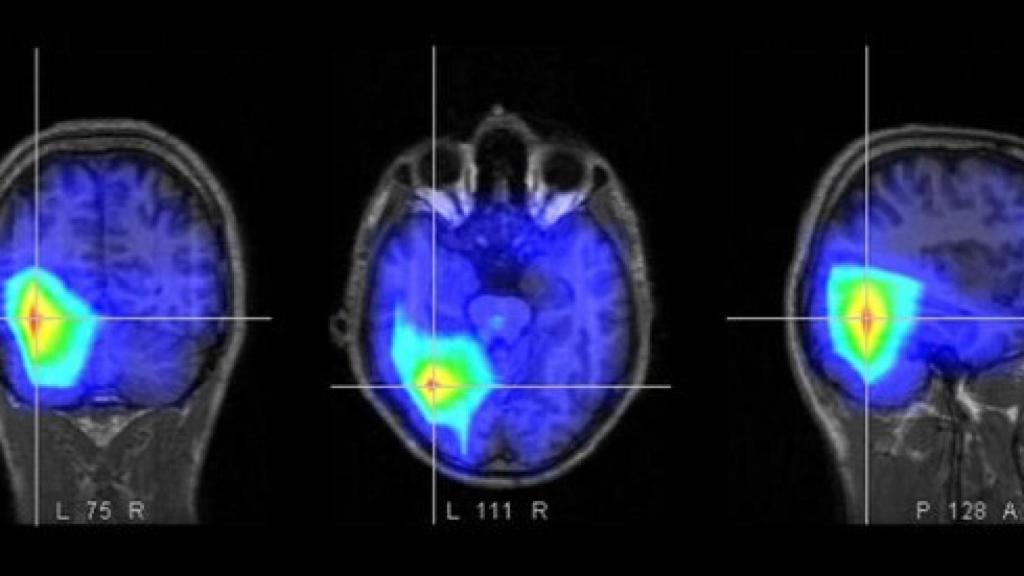

Para poder comparar a los pacientes, Achard y sus colegas usaron imágenes de resonancia magnética funcional (fMRI), escaneando el cerebro de 17 pacientes en coma tras varios días después de un paro cardíaco, y comparándolos con 20 voluntarios sanos en reposo. Algunos de los que habían estado sin oxígeno cerebral durante 30-40 minutos, se recuperaron, pero más de la mitad murieron.

Durante el estudio, se examinaron hasta 417 regiones cerebrales diferentes para detectar el flujo sanguíneo (un buen marcador de actividad cerebral, relacionado con aumento o disminución de la actividad). En los pacientes sanos, entorno a unas 40 regiones se iluminaban simultáneamente con muchas otras partes del cerebro, eran los centros de “alto tráfico”, que procesan gran parte de la información cerebral. Pero, en lo pacientes en coma, muchos de estos centros estaban oscuros, y se iluminaban algunas zonas periféricas en su lugar. Concretamente, en una zona llamada precuneus (muy importante en la conciencia y la memoria), había menos centros activos.